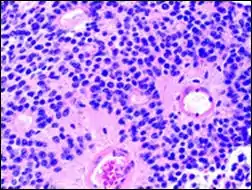

Micrograph of an ameloblastoma showing characteristic palisading. H&E stain.

Palisades that are generally longer than a rosette or pseudorosette can be seen in neural tumors such as Schwannoma,[16][17] as well as in ameloblastomas. It can also be seen in nodular basal-cell carcinomas.[18]